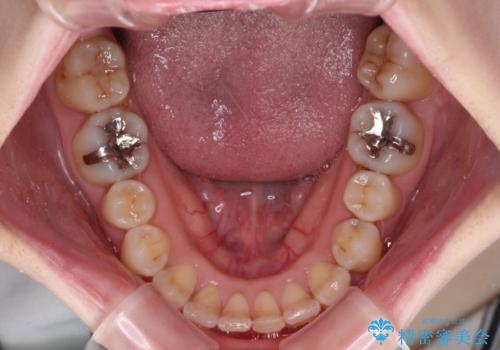

- 前歯のデコボコをクロスバイトを気にして来院された患者様です。

上顎骨の横幅が狭く、上下ともに内側に倒れ込んだ混み合った歯列となっていました。